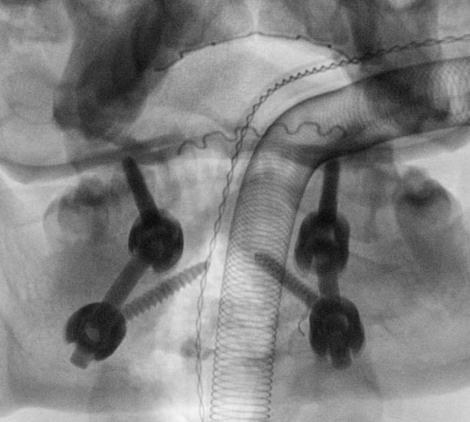

C1/C2 fusion

Technique

Goel Harms

- C1 lateral mass screw

- C2 pedicle screw monocortical to reduce risk of vertebral artery injury

- preoperative CT angiogram important

- must avoid medial penetration of canal

Surgical technique PDF C1 C2 fusion

Vumedi technique Goel-Harms C1/C2 fusion

C1 2 fusion 1C1 2 fusion 2